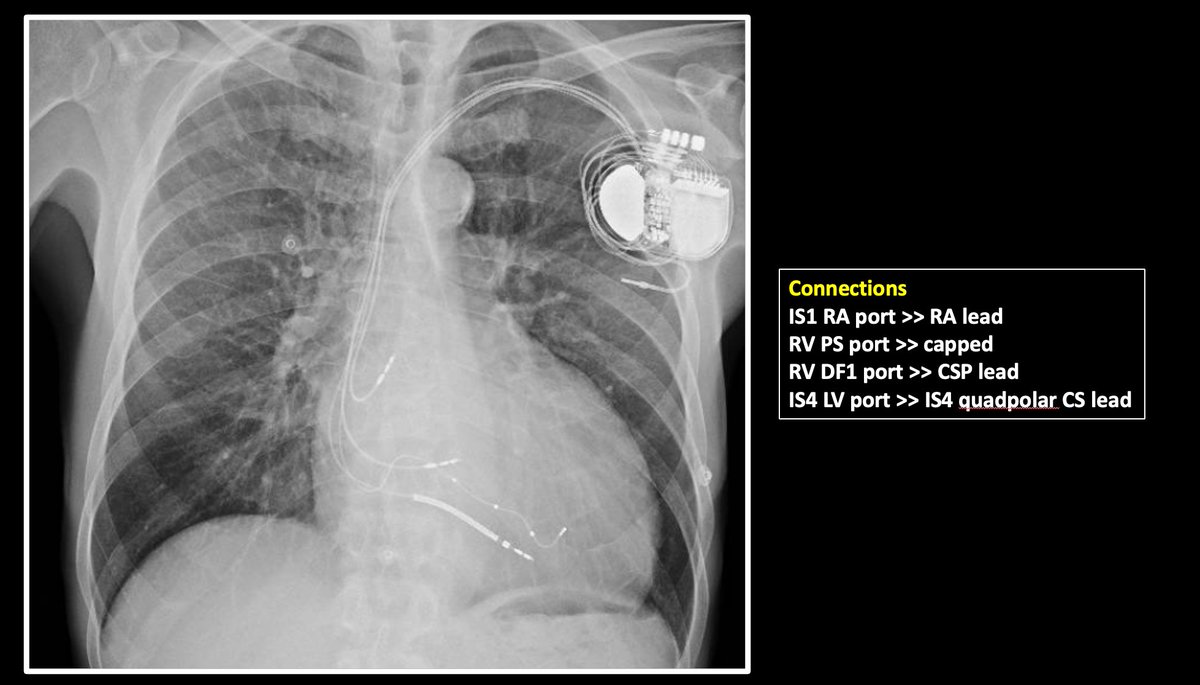

5/ This was the final optimised result with both LBB and CS lead pacing, and after adjusting VV plus the AV delay (which Biotronik allows via the autoAdapt %). It does look very good, with a QRS of around 110ms. But what if I had only used a CSP lead (or CS lead)?

4/ Identified a good lateral branch which gave usable thresholds, and selected that. Confirmed electrical delays to that spot was good (140ms). So now had to decide between conventional CRT, LBB-CRT or LOT-CRT. I succumbed to choosing a LOT-CRT. Was this a smart choice?

3/ Some key moments shown here. Used a RBB knock test to induce temporary CHB to confirm there *was* LBBB. Started w/LBB lead. However, LVAT on right septum was massive 170ms, and although it dropped++ to 104ms on crossing to left, it was still long >> not happy to accept this.

1/ I wonder what #Epeeps would do for a 62yo male patient with NICMP, LBBB QRSd >200ms, LVIDd 71mm, LVEF12%? Conventional CRT, LBB-CRT, LOT-CRT, too advanced for CRT? For CRT, any vendor preferences? @finnakerstrom @James_Elliott01 @enes_elvin @riley_guntrip @chris_monkhouse